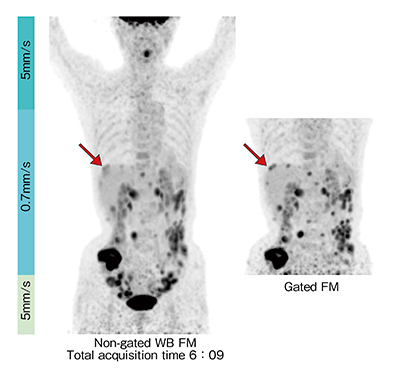

FM法では,1回の全身撮像データを用い,病変の描出に適した任意の再構成範囲と条件を用いることにより,読影医の必要に応じた画像を撮像後のデータから作成することができる。図2の症例では,1回の撮像から,通常マトリックス画像と腹部の高マトリックス画像を再構成した。高マトリックス画像は,点在する病変の描出が優れており,これらの画像は約11分半の撮像データから追加撮像なしに得ることができた。図3に示す上行結腸がんの肝転移症例では,撮像時間6分程度で,全身画像および呼吸同期画像の双方を得ることができた。従来法では,追加撮像のために検査時間の延長が懸念される呼吸同期撮像であるが,FM法と組み合わせることにより,全検査において呼吸同期信号を収集しておき,後処理の一部として必要に応じて呼吸同期再構成を行うという臨床手技が実用的に可能となった。

図3 上行結腸がん肝転移,腹膜播種

呼吸同期法により肝臓上葉辺部の2つの集積(→)が明瞭に区別できる。

(画像ご提供:慶應義塾大学病院様)